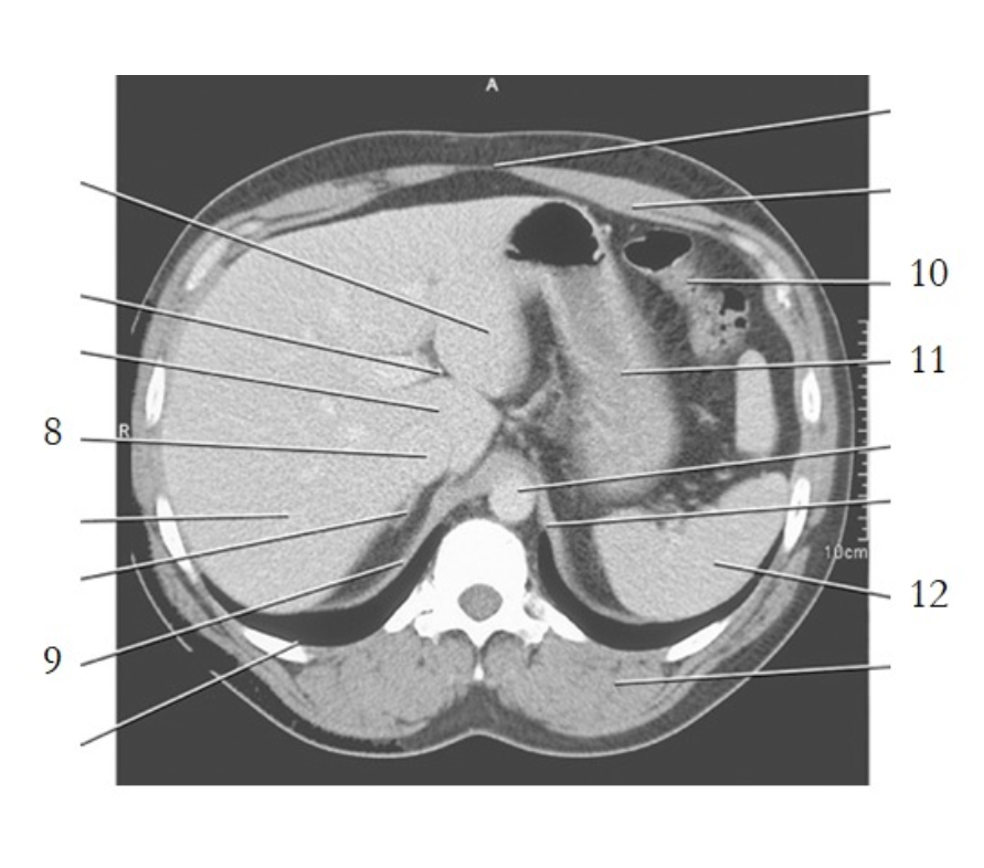

liver

esophagus

stomach

spleen

crus of diaphragm

IVC

pancreas tail

kidney

gallbladder